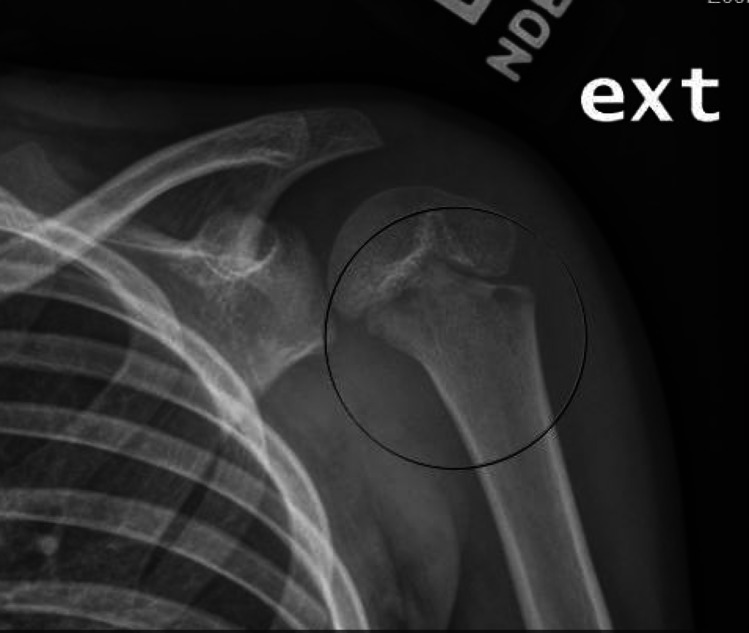

Purpose of review: For pediatric osteomyelitis and septic arthritis, 10-24% of cases occur in the upper extremity (UE). Due to delays in presentation and diagnosis, UE infections are often more complex and severe than infections of the lower extremity (LE). This review evaluates the literature from the past 6 years related to pediatric osteomyelitis and septic arthritis of the UE and provides a guide for professionals managing these conditions in children.

Recent findings: The shoulder and elbow are the most commonly affected joints, and the humerus is the most commonly affected bone. As with the LE, diagnosis of UE osteoarticular infections is based on clinical evidence, laboratory data, and diagnostic imaging. While Staphylococcus aureus is the primary bacteria identified in UE infections, there is an underappreciation of the burden from Kingella kingae as a causative organism in culture-negative patients where PCR is not performed. Septic joints should be treated with irrigation and debridement urgently, with subsequent antibiotic therapy for a minimum of 2-4 weeks. For acute osteomyelitis without abscess or concomitant septic joints, antibiotic therapy is standard of care. Methicillin-resistant Staphylococcus aureus is associated with more severe infection requiring more surgeries. Various strategies exist for managing segmental bone loss in chronic osteoarticular infections. Osteomyelitis and septic arthritis tend to occur less frequently in the UE than the LE but have a devastating impact on the health and quality of life of children around the world. Complete resolution of disease can be achieved through an individualized approach to antibiotic and operative management. Further study is needed to assess the efficacy of aspiration as a primary treatment strategy in UE joints.